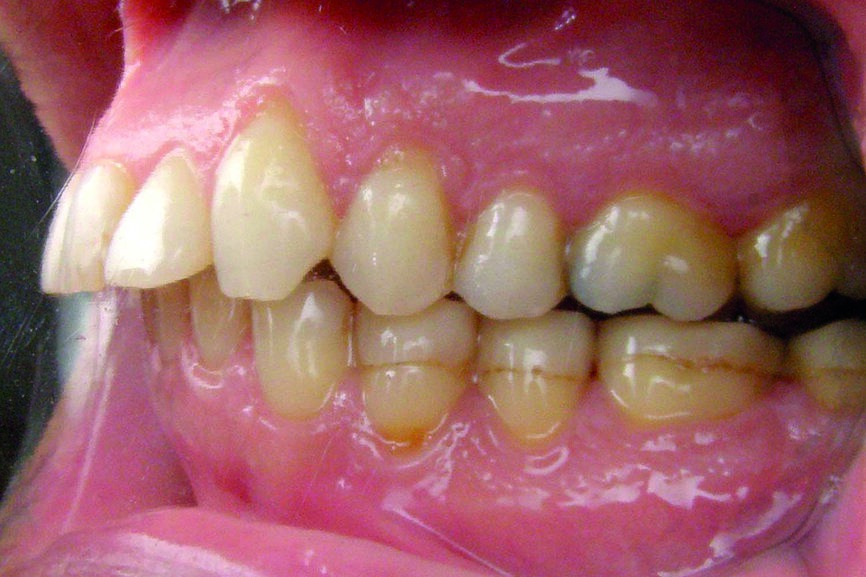

Examen des arcades

D’un point de vue dentaire le patient présente une Classe II division 1, avec une classe II molaire complète et une classe II canine.

- Présence d’un overjet et d’une supraclusion résiduelle.

- L’arcade supérieure est régulière mais les incisives sont en vestibulo version importante.

- L’arcade inférieure présente un encombrement dans le secteur antérieur associé à une version vestibulaire.

- Les milieux correspondent.